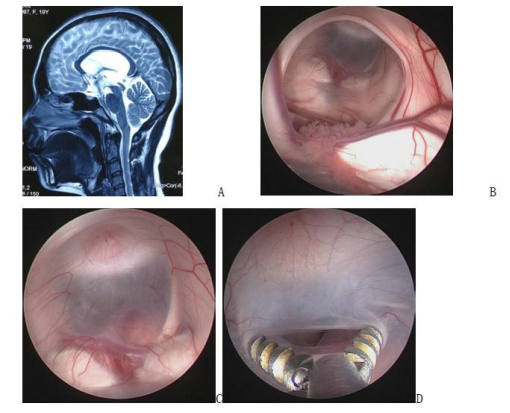

Figure 5. A preoperative magnetic resonance image; B intraoperative screenshot, endoscopically visible periventricular foramen structures; C, D base of the three ventricles and fistula (basilar artery visible below the fistula)